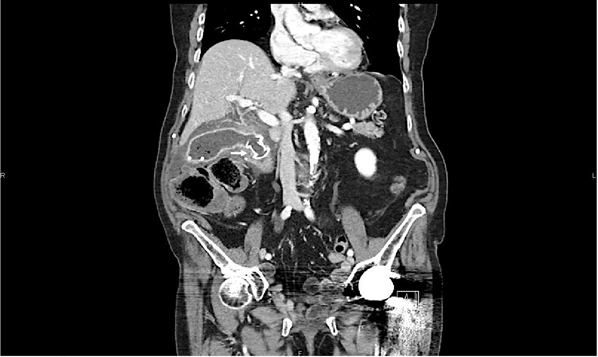

However, three months later, the patient experienced recurrent cholecystitis. Surgical cholecystectomy was considered but deemed too invasive for this frail elderly patient. As a result, we opted for EUS-guided gallbladder drainage, creating a cholecysto-bulbostomy and inserting a 15 mm diameter Lumen Apposing Metal Stent (LAMS) (Figure 1). Subsequently, a double-pigtail plastic biliary stent was placed through the LAMS to ensure correct LAMS stability. Unfortunately, the procedure was complicated by pneumoperitoneum, which we promptly addressed with needle exsufflation. Fortunately, the patient exhibited a positive clinical response while hospitalised and was consequently discharged.

Figure 1 Abdominal CT image of EUS-guided gallbladder drainage, showing the creation of a cholecysto-bulbostomy and inserting a 15 mm diameter Lumen Apposing Metal Stent (LAMS), as indicated by the arrow.